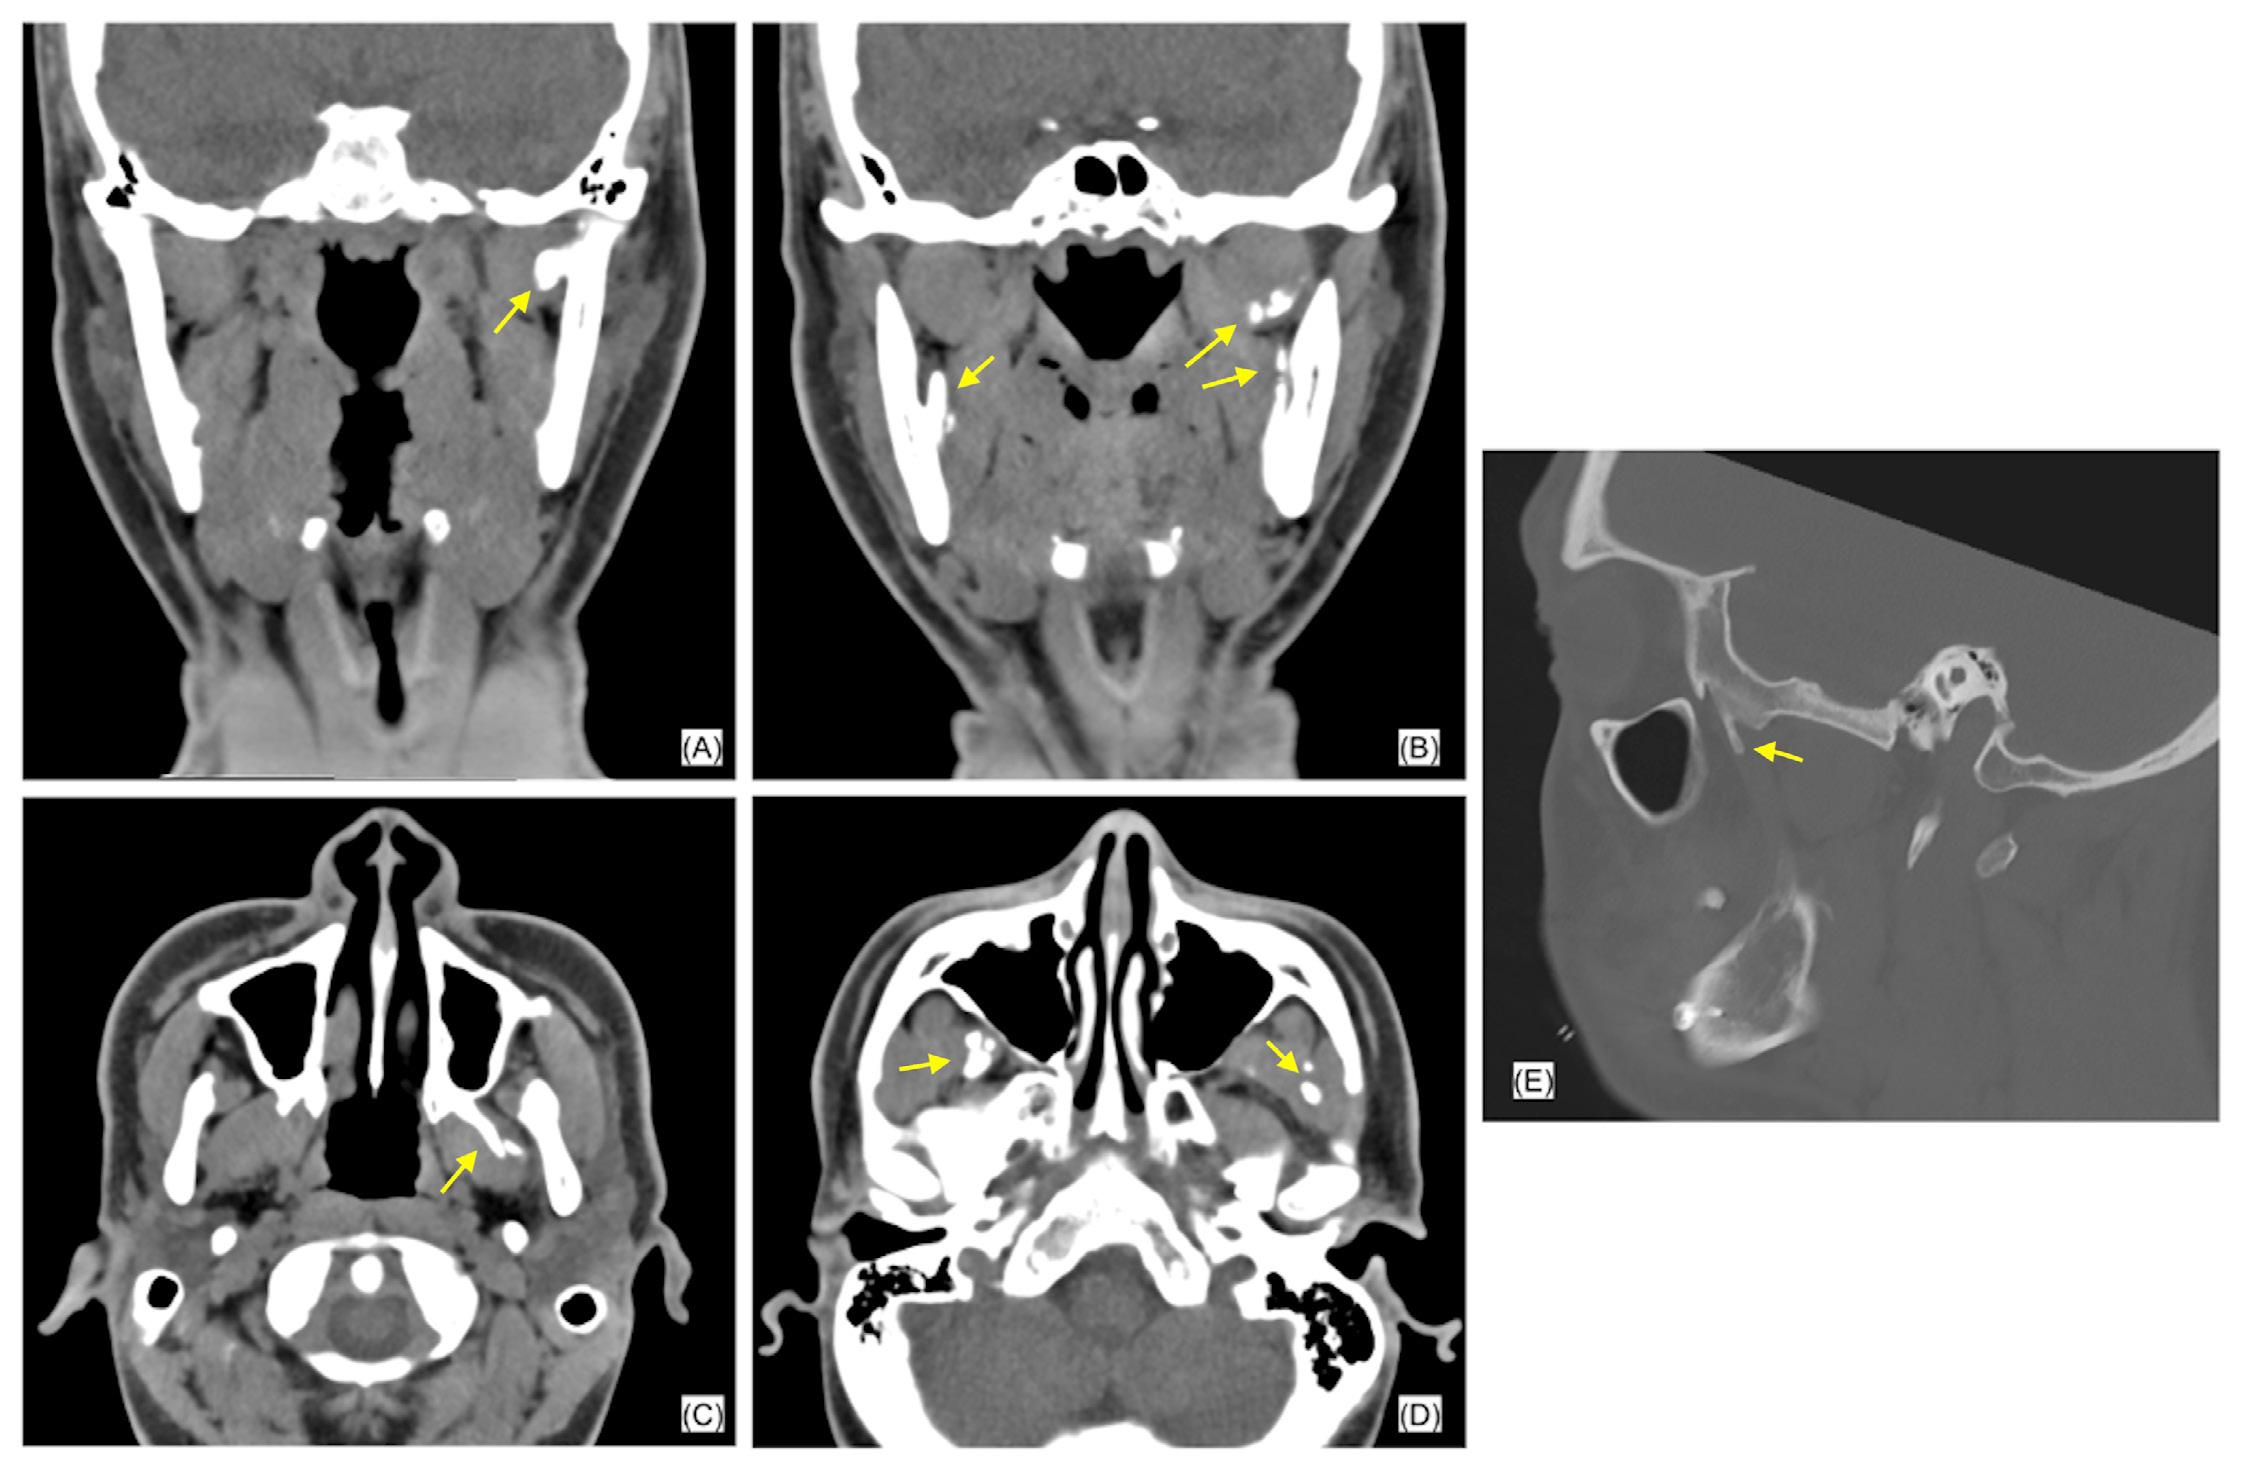

Treatment planning protocol was the same for all individuals and included examination, impressions for study models and a clinical bite record using wax and captured in centric relation (CR, the condyle was in the most superior and posterior position in the glenoid fossa). The clinical bite records and study models were subsequently digitised. A pre-operative medical-grade helical CT image was captured with the individual in a supine position with their lips closed, ensuring gentle occlusion in centric occlusion (CO, the position of maximum intercuspation of the dentition) without a bite registration splint. The CT protocol was derived from KLS Martin Group (KLS Martin Group, Germany) including special resolution of 0.5–1.25 mm and gantry tilt of 0°. A virtual skull model was created for each individual by a clinical engineer using Materialise Magics three-dimensional printing software (Materialise, Belgium). This process involved two steps with collaboration between the clinical engineer and the surgeon pivotal in forming the surgical plan, a dynamic process tailored to each patient’s unique requirements, outlined in Figure 1

2. Superimposed digital reconstruction skull images from Materialise Magics with the planned final outcome in orange and the post-operative scan data in green

Seventeen individuals (12 females, age range between 18 and 61 years) satisfied the inclusion criteria. The number of patients in each surgery type (maxillary, mandibular, bimaxillary) is presented in Figure 3

The disparities between the anticipated positions of selected landmarks and their actual post-operative locations in both singlejaw and bimaxillary surgeries are summarised in Table 2

For the maxillary surgeries, the mean combined difference between anticipated movements and final position along the x, y and z axes was compared between single-jaw (1.33 ± 1.12 mm) and bimaxillary surgeries (1.33 ± 1.30 mm), as seen in Figure 4. An independent samples t-test revealed no statistically significant difference between single-jaw and bimaxillary surgeries (t(210) = 0.01; P = 0.992). The mean combined difference between anticipated movements and final position along the x, y and z axes in the mandible for single-jaw (1.00 ± 1.20 mm) and bimaxillary surgeries (1.75 ± 1.47 mm) was calculated (Figure 5). An independent samples t-test indicated a significant difference (t(257) = 4.91; P < 0.001; d = 0.54).

Three-dimensional linear measurements ranged between a mean of 0.86 mm for the lower right mandibular molar in single-jaw surgery

and 5.75 mm for the pogonion in bimaxillary surgery. Levene’s test did not reveal any statistically significant difference among the variances of the maxillary landmarks in either single-jaw or bimaxillary surgeries (single jaw: F(5, 84) = 0.53, P = 0.752; bimaxillary: F(5, 138) = 0.37, P = 0.871). However, a significant difference was noted between mandibular landmarks in both single-jaw and bimaxillary surgeries (single jaw: F(8, 88) = 4.85, P < 0.001; bimaxillary: F(8, 207) = 2.96, P = 0.004). A significant difference in variance occurred between single-jaw and bimaxillary surgeries in the mandible (F(1, 322) = 7.93; P = 0.005), but not in the maxilla (F(1, 232) = < 0.001; P = 0.996) and not between the maxilla and mandible in single-jaw operations (F(1, 196) = 2.57; P = 0.110) or bimaxillary operations (F(1, 358) = 1.51; P = 0.220). There was a heterogeneic variance among the x, y and z axes in the maxilla in both single and bimaxillary surgeries (single jaw: F(2, 87) = 6.50, P = 0.002; bimaxillary: F(2, 141) = 6.28, P = 0.002), but not in the mandible (single jaw: F(2, 105) = 0.13, P = 0.883; bimaxillary: F(2, 213) = 0.32, P = 0.729).

This article shows that this simplified method of VSP assessment results in a clinically accurate assessment for orthognathic surgery. The accuracy from the planning protocol is derived from segmentation of the CT imaging to incorporate digitised scanned occlusion. Deviations from this position could pose challenges for clinical engineers in determining the correct condylar position, leading to a notable variance between the planned and actual outcome for CoR

and CoL points. Accurate data collection before formulating the surgical plan, including the capture of impressions and centric relation clinically is crucial, as any errors in this phase would propagate through the planning process. This simplified protocol not only achieves clinically acceptable outcomes but also improves surgical and pre-operative efficiency by reducing technique sensitivity, requiring only one consultation appointment, eliminating the need for guide splints, and streamlining the process with a single preoperative radiographic scan.

Most mean landmark variances, except for three, and all median values except one, remained below the 2-mm threshold recognised as clinically significant.19 The findings of this study demonstrate favourable outcomes in the maxilla, both for singlejaw and bimaxillary surgeries, with greater accuracy of maxillary landmark positions (mean, 1.09–1.51 mm). Therefore the maxillary position on the CT scan is not influenced by the position of the condylar seating at the time of the scan. In contrast, the mandibular movements had greater variations in the accuracy of landmark positioning. Landmarks anterior to the osteotomy in the proximal segment of single-jaw surgery (B, mandibular mid-incisor point [Md], Pog) exhibited minimal variance between their planned and actual postoperative positions (mean, 0.43–0.61 mm). However, the points in the distal segment (CoL, CoR, GoL, GoR, lower left first molar [LLM], lower right first molar [LRM]) had larger discrepancies (mean, 1.21–2.34 mm). Notably, GoL exceeded the 2-mm threshold for clinical acceptability.19 This may be explained by intraoperative seating of the condyle being potentially varied from the predicted seating of VSP; influenced by soft tissues within the temporomandibular joint, perimandibular musculature, alignment of the lower border of the mandible and control of torsional movements of the proximal segment.

During bimaxillary surgery, the mandible exhibited the highest degree of variance, particularly at Pog (2.89 mm) and GoL (2.19 mm) and GoR (1.62 mm). This is expected due to the compounded nature of any discrepancy from the initial maxillary movement and fixation position before mandibular movement. Previous studies